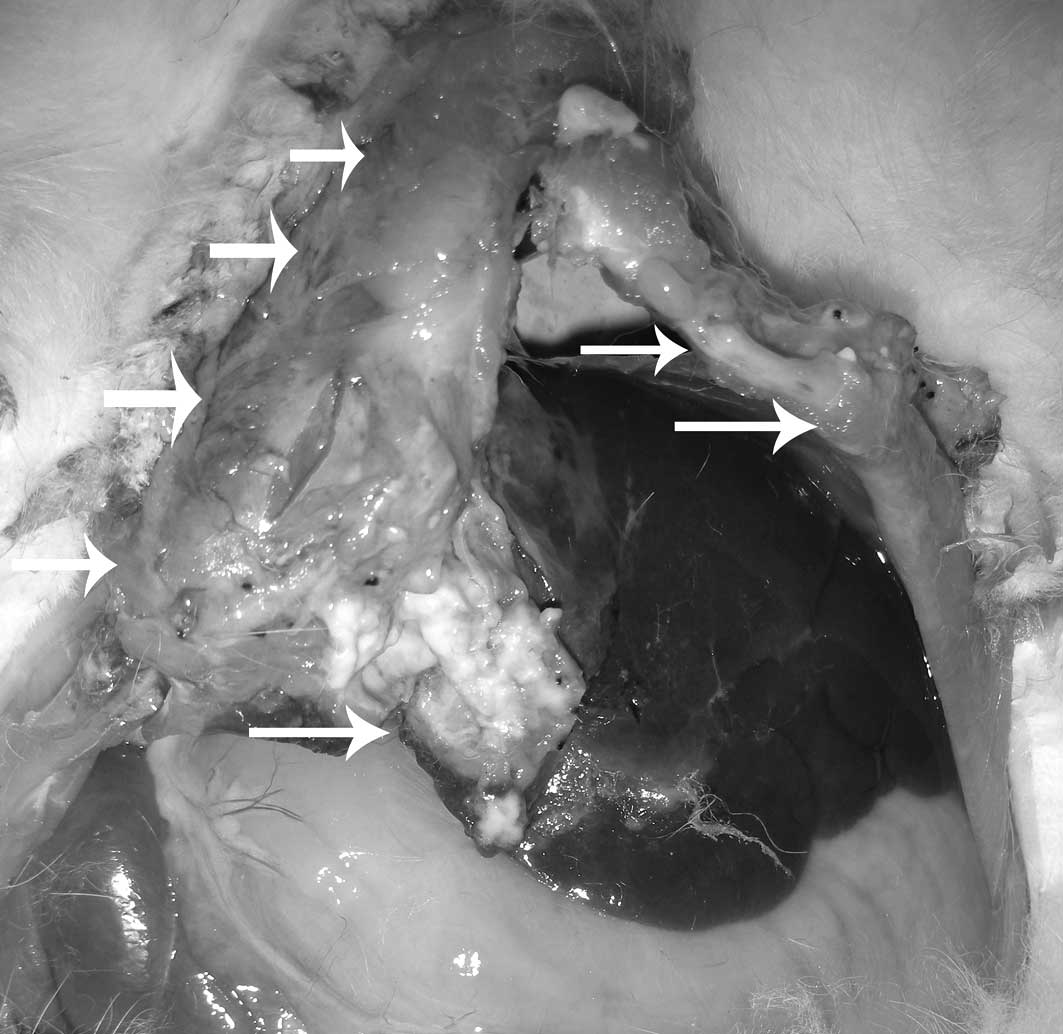

In group 1, 8 rabbits displayed no evidence of liver tumor growth at 2 weeks following implantation. Liver tumors were grown in 14 out of 22 rabbits with an overall success rate of 63.6%. In group 2, only 1 rabbit displayed no evidence of liver tumor growth. Successful liver tumor growth was achieved in 21 out of the 22 rabbits with an overall success rate of 95.5%. Upon further sub-analysis, single nodular tumors in the liver were observed in 4 out of 14 rabbits in group 1 (28.6%) and 14 out of 21 rabbits in group 2 (66.7%) (Figs. 2–5). Multinodular tumors in the liver were grown in 10 out of 14 rabbits in group 1 (71.4%) and in 7 out of 21 rabbits in group 2 (33.3%) (Fig. 6). In addition, extrahepatic metastases were observed in 5 out of 14 rabbits in group 1 (35.7%) and in 1 of 21 rabbits in group 2 (4.9%) (Fig. 7). There were statistically significant differences between the 2 groups. The overall liver tumor growth rate of group 1 was significantly lower than that of group 2 (P=0.025). Furthermore, the single nodular tumor growth rate of group 1 was significantly lower than that of group 2, and the multinodular tumor growth rate of group 1 was significantly higher than that of group 2 (P=0.041). Finally, a higher incidence of extrahepatic metastasis was observed in group 1 (P=0.028).